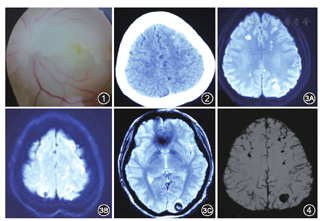

患者女性,29岁,主因"左眼失明伴头痛头晕3 d"于2016年6月28日入住我院。患者于2016年6月24日下午在美容诊所行鼻背部玻尿酸注射隆鼻术时突发左眼失明,同时伴头晕、头痛及全身乏力,外院查眼底提示左视网膜中央动脉(CRA)阻塞(图1)。当日头颅CT提示左额叶脑沟内高密度影,不排除出血(图2)。6月25日查血常规、血生化、凝血+D-二聚体示:白细胞18.54×109/L,中性粒细胞90.9%,淋巴细胞7%,肌酸激酶1 008 U/L,超敏C反应蛋白(HR-CRP) 9.41 mg/L(正常值:0~3 mg/L),ALT 26 U/L, AST 33 U/L,凝血+D-二聚体未见明显异常。6月27日复查血常规及生化示:白细胞13.49×109/L,中性粒细胞73.7%,淋巴细胞18.8%,AST 63 U/L,肌酸激酶1 201 U/L, ALT 29 U/L,HR-CRP 8.13 mg/L。6月27日上午在外院行玻尿酸溶解酶球后注射术,术后头颅MRI提示:双侧额、颞、顶、枕叶皮质下白质内及右侧尾状核头区内多发梗死灶,双侧顶叶及左侧枕叶多发异常信号,考虑为出血(图3A,图3B,图3C),头颅MRA未见明显异常。为求进一步诊治,于6月28日入住我科。体检:意识清楚,言语流利,鼻背部可见斑片状紫色瘀斑。左眼结膜轻度充血。粗测左眼视力为0,无光感,左侧瞳孔直径约5 mm,直接、间接对光反射消失,右侧瞳孔直径3 mm,直接对光反射灵敏,间接对光反射消失;双眼同轴居中,左眼外展内收欠充分,左眼上视下视尚可,未见眼震;双侧足跖反射中性,余未见明显异常。既往体健。入院诊断:脑梗死伴出血,TOAST分型考虑为其他原因型。入院后复查头颅DWI+磁敏感加权成像+磁共振静脉造影(MRV),提示颅内多发出血灶,较前变化不大(图4),MRV未见明显异常,颈动脉、椎动脉、锁骨下动脉超声未见明显异常。心脏发泡试验示:未见右向左分流。复查血:白细胞17.15×109/L,中性粒细胞68.5%,淋巴细胞24.2%,ALT 114.4 U/L,AST 81.5 U/L,肌酸激酶882 U/L。入院后给予营养神经、高压氧等治疗,患者头晕、头痛症状完全消失,左眼视力未见明显改善。